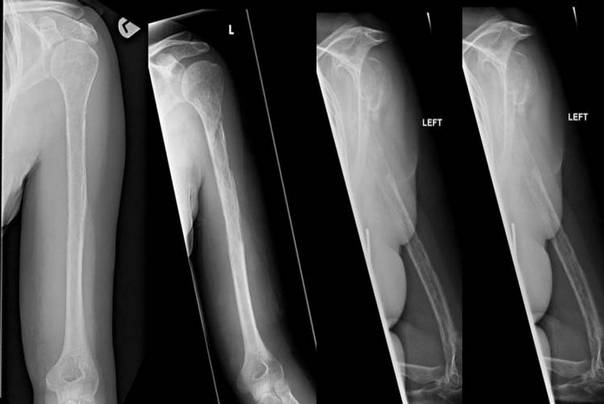

Sa ovim retkim (za lekare) misterioznim sindromom – bolesti su se nedavno susreli lekar u Edinburškoj bolnici u Škotskoj bolest se pojavila kod s jedne nemenovane 44-godišnje žene

Gorham-Stout(ov) sindrom je od kojeg je patila žena, bolest koja se javlja kada kosti same nestaju u telu. Ovo je redak fenomen u kojem ljudi progresivno i rapidno gube kosti.

Kost zamenjuju beningni odnosno nekancerogeni tumori krvnih sudova. Agonija kod ove žene je trajala otprilike godinu i po, pojavila se tako da je prvo osećala jaku bol u rukama, odnosno da ima otok.